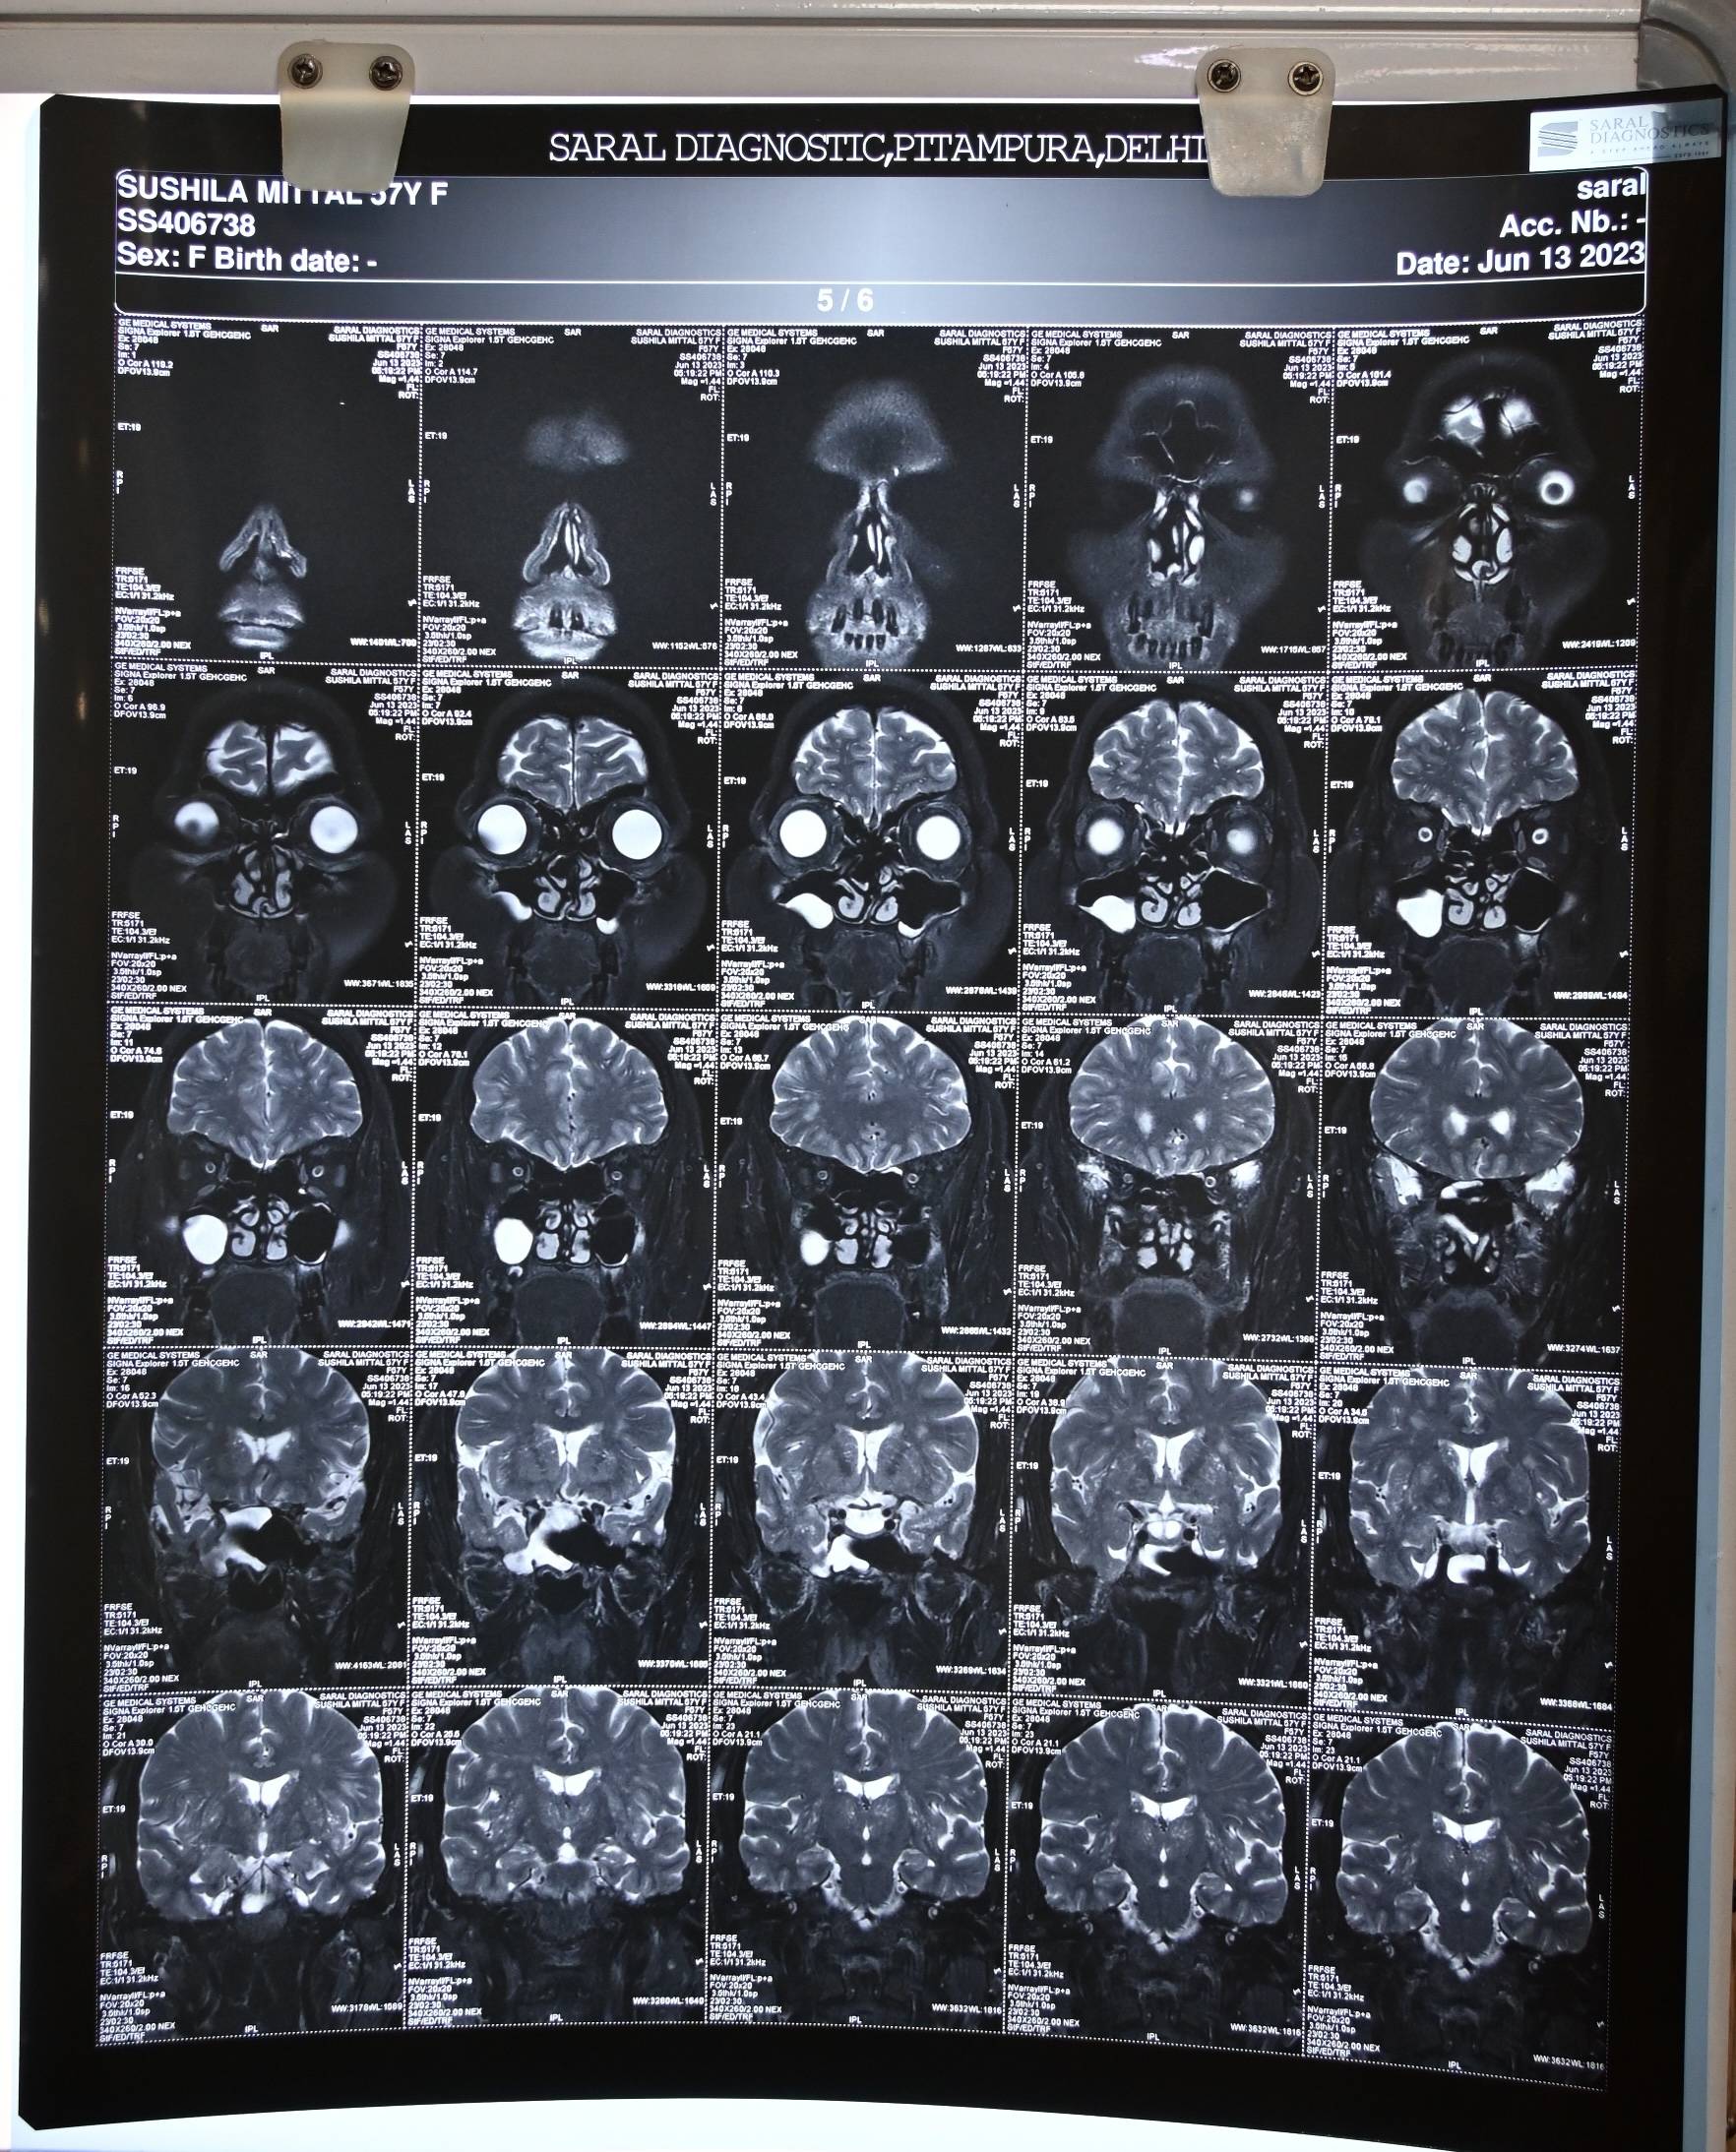

The patient was examined by an ENT surgeon and underwent an MR cisternography with contrast, which confirmed the clinical diagnosis. The report revealed two osseo-dural defects along the posterior wall of the lateral recess of the right sphenoid sinus, measuring approximately 3.1 mm and 2.4 mm, with small herniations of brain parenchyma measuring about 5 mm at both sites. The right sphenoid sinus and its lateral recess were filled with fluid revealing an isointense signal to CSF.